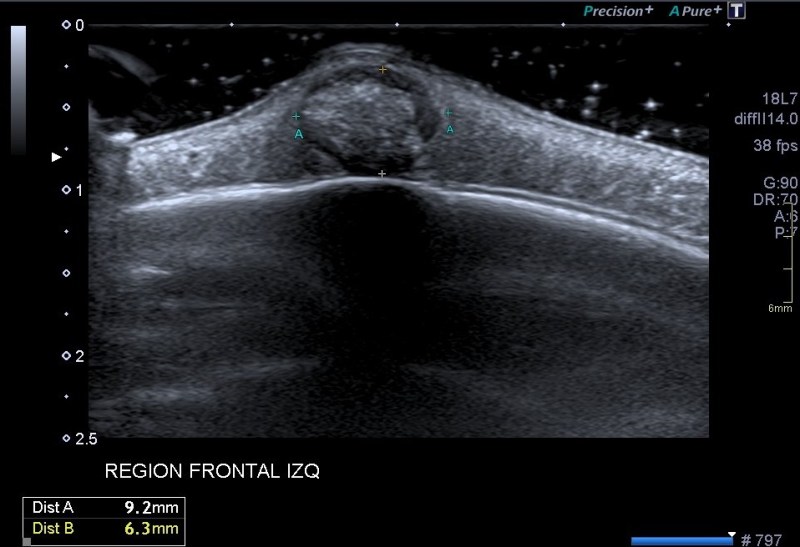

Lo primero que quiero que tengas en cuenta es la localización del bulto, ves que es supersuperficial. Para estudiar este tipo de lesiones lo que debes hacer es tener una buena capa de gel sobre el tumor. Esto se hace con efecto de apoyar la sonda sobre el gel y no sobre la piel para no deformar la lesión, así que es muy importante la técnica y pericia de la operadora que esté ejecutando el estudio.

Lo segundo es localizarlo perfectamente en su ubicación, y ver a qué planos pertenece, si está tocando o no la estructuras que están a su alrededor. En el caso de esta lesión vemos que está en justo debajo de la piel, en el escaso espesor de tejido celular subcutáneo que existe en la región frontal, que es donde la mujer tenía este tumor.

Tercero y último. Ahora lo medimos y lo estudiamos ecográficamente, acotándolo. La semiología es importante, en este caso, el tumor tiene un aspecto hipoecogénico, pero en el centro es hiperecogénico, pero además, dentro de esta hiperecogenicidad existe un grado más de hiperecogenicidad perteneciente a una calcificación grosera. Sus bordes son definidos y con la salvedad de las zonas de calcio, el tumor transmite bien. Su aspecto es heterogéneo, no presenta vascularización, la que ves en la imagen es artefacto de aliasing provocado por el calcio de la lesión.

En estos casos donde el tumor está tan cerca del hueso hay que asegurarse de que éste está indemne. Se demuestra que la lesión no afecta al hueso y que está circunscrita al ámbito puramente subcutáneo.